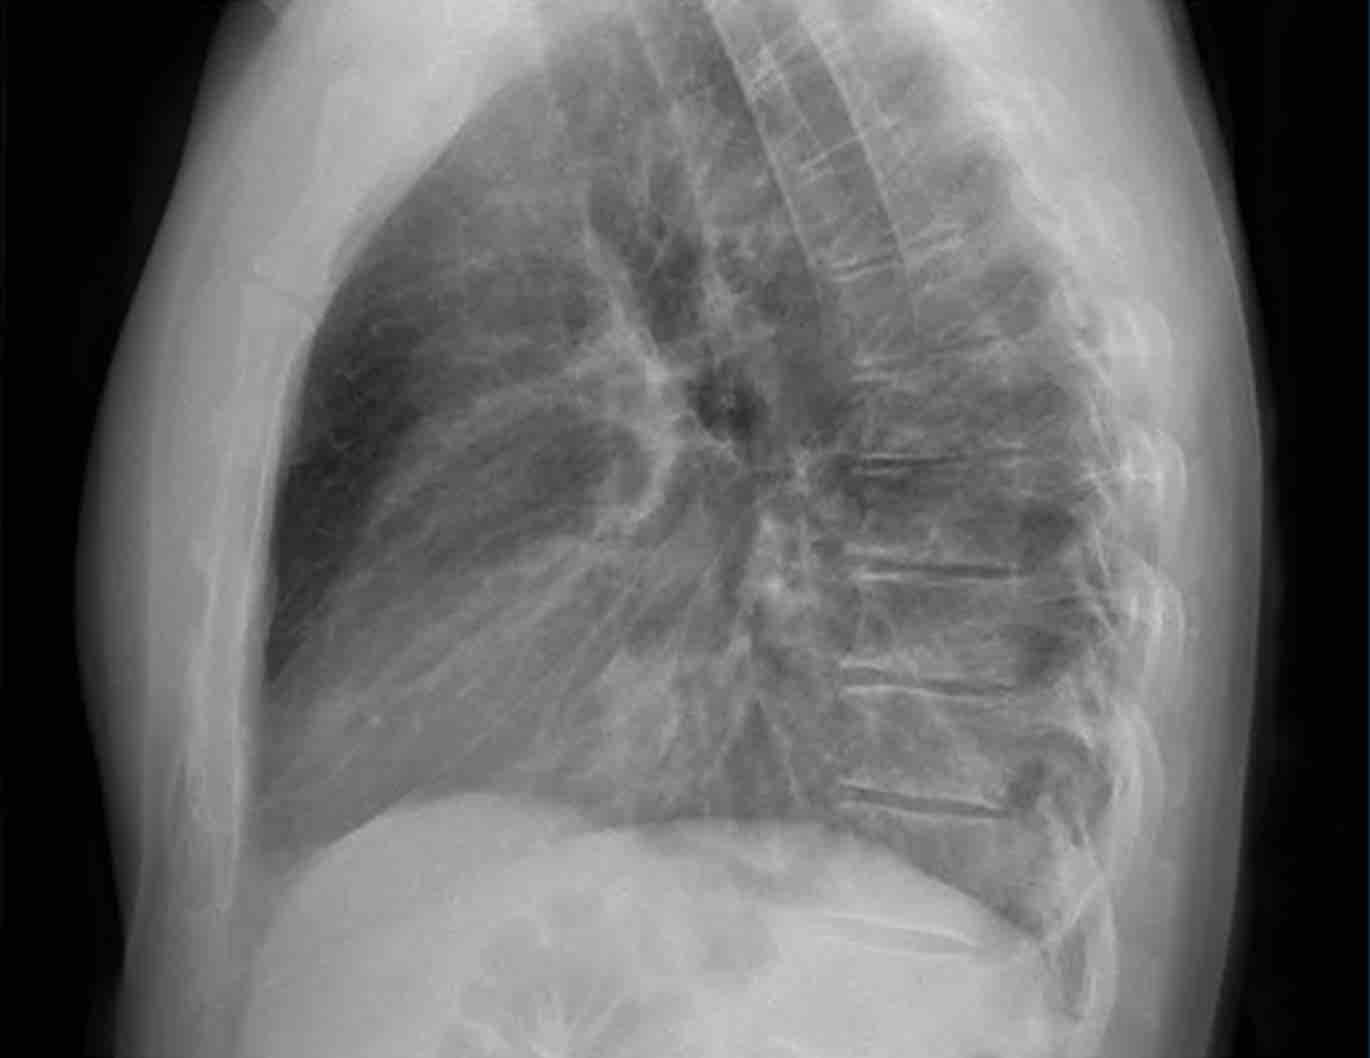

Tư thế nghiêng

Trên phim X-quang ngực tư thế nghiêng, các bờ tim cần được xác định rõ ràng, và tĩnh mạch chủ dưới (IVC) thường có thể thấy đổ vào nhĩ phải.

Khoang sáng sau xương ức

Khoang sau xương ức bình thường chứa phổi có khí và do đó phải có hình ảnh thấu quang (tối trên phim), kéo dài xuống dưới đến mức thất phải tiếp xúc với xương ức (mũi tên đen nhỏ).

Bất kỳ hình mờ nào trong khoang sau xương ức phía trên đều đáng ngờ về tổn thương trung thất trước hoặc khối xuất phát từ các thùy trên của phổi.

Dấu hiệu cột sống

Khi đánh giá các thân đốt sống trên tư thế nghiêng, chúng phải có hình ảnh thấu quang (tối hơn) tăng dần từ trên xuống dưới do lượng phổi có khí chồng lên ngày càng nhiều (mũi tên trắng).

Nếu các đốt sống ngực dưới có hình ảnh đậm bất thường, điều này có thể gợi ý bệnh lý ở các thùy dưới, chẳng hạn như đông đặc hoặc khối — đây được gọi là dấu hiệu cột sống.

Đánh giá Cơ hoành

- Vòm hoành phải phải được nhìn thấy rõ ràng ở phía trước đến tận thành ngực (mũi tên đỏ), thể hiện ranh giới giữa phổi có khí và mô mềm ổ bụng.

- Vòm hoành trái thường chỉ nhìn thấy đến điểm tiếp giáp với bóng tim (mũi tên xanh lam), phía ngoài điểm đó ranh giới bị mất do tỷ trọng tương đương giữa tim và các tạng bụng phía trên.